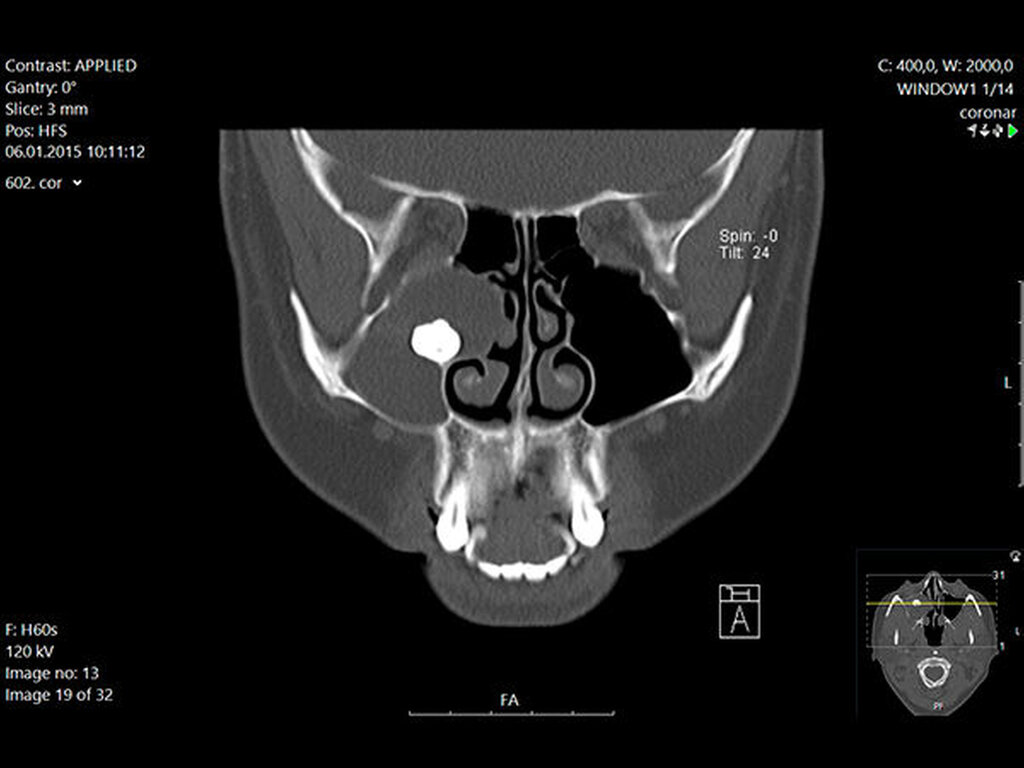

In der regionalen Klinik (Winterberg-Krankenhaus Saarbrücken) wurde zusätzlich eine kontrastmittelunterstützte Computertomografie der Nasennebenhöhlen durchgeführt (Abbildungen 2 und 3), die den Befund bestätigte und präzisierte.